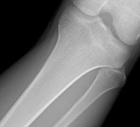

Case 4

16 year old male c/o 9 months of left knee pain

Zoom image: Radiological image Radiological image.